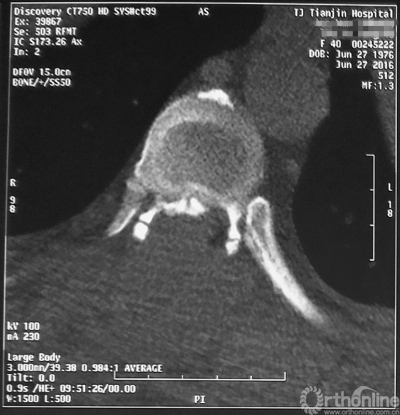

术前CT

家人曾带她辗转当地治疗,因病情复杂没有得到有效的治疗,于是慕名找到天津医院脊柱外科二病区主任苗军博士诊治,当苗军主任看到躺在担架上的刘女士痛苦的表情和渴望健康的眼神,他决定收她入院为其进行手术治疗。入院检查发现,刘女士患有多节段胸椎管狭窄症,以胸8-9节段严重,椎管狭窄达80%,脊髓已严重变性。